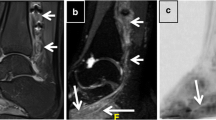

Using a Philips Achieva 3 T and the product 15-channel SENSE spine coil, the lumbosacral spine was imaged coronally using the 3D ‘nerve-SHeath signal increased with INKed rest-tissue RARE Imaging’ (SHINKEI) sequence6,7, as follows: TR = 2,500 ms; TE = 192 ms, FOV = 180 × 180 mm2, voxel size = 1 × 1 × 1 mm3, number of averages = 1, TSE factor = 100, iMSDE duration = 50 ms, 81 slices, scanning time of 10:20 min. The imaging volume was positioned at the superior margin of the L2 vertebral body with the volume extending caudally towards the sacral segments, to ensure coverage of L2-L5 segments in all subjects (Fig. 1); an example image is shown in Fig. 2A,B. MTR imaging was performed using identical scan geometry to the SHINKEI acquisition as follows: 3D FFE dual-echo ‘stack of stars’ (TR / TE1 / TE2 = 36 / 1.56 / 2.7 ms; flip angle α = 10°), with and without Sinc–Gaussian shaped MT saturation pulses with nominal α = 360°; offset frequency = 1 kHz, and duration 16 ms; number of slices = 81; FOV = 180 × 180 mm2; voxel size = 1 × 1 × 1 mm3; scanning time of 10:45 min.

Imaging volume (yellow) and shim box (red) prescription using the 3D ‘nerve-SHeath signal increased with INKed rest-tissue RARE Imaging’ (SHINKEI) sequence, starting from the superior margin of the L2 vertebral body extending caudally towards the sacral segments, to ensure coverage of L2–L5 segments in all subjects. Positioning of anterior and posterior saturation slabs is also shown (blue).

Example images obtained using the ‘nerve-SHeath signal increased with INKed rest-tissue RARE Imaging’ (SHINKEI) sequence showing (in the superior-inferior direction) (A) the L2–L4 segments and (B) the L5 segment; (C) annotated binary masks were drawn manually for each segment (L2, L3, L4) and (D) L5, to distinguish between the preganglionic, ganglionic and postganglionic regions.